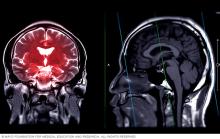

Magnetic resonance imaging (MRI) brain scan showing highlighted areas

T2-weighted and T1-weighted brain magnetic resonance imaging (MRI) scans. These images can help diagnose brain conditions such as tumors, multiple sclerosis and stroke.